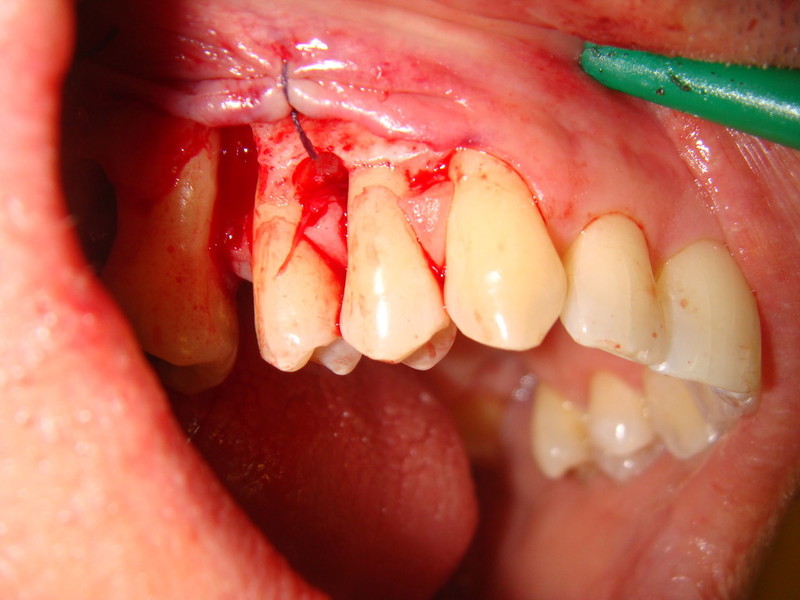

Chirurgia plastica Muco-Gengivale